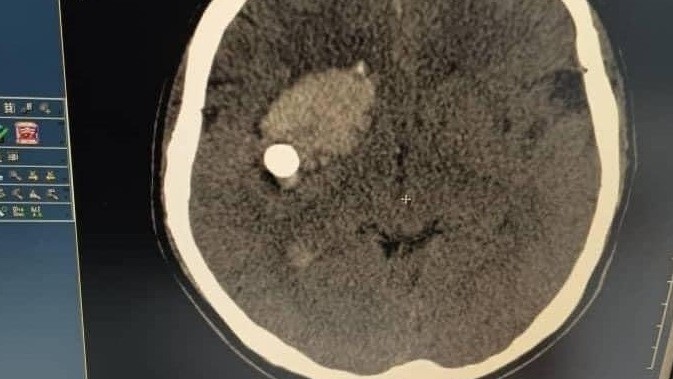

AKIPRESS.COM - A 7-month-old baby in Alay district of Osh region was seriously injured when his 7-year-old brother accidentally shot him with a shooting range at home...